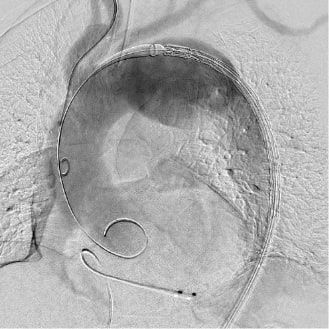

ステントグラフト挿入前